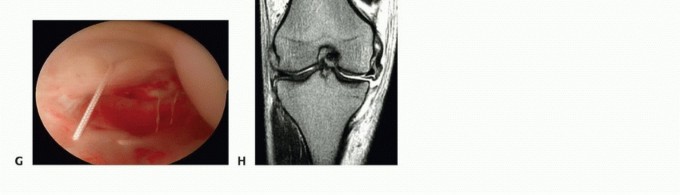

FIG 1 • (continued)D. Additional image of arthroscopic ipsilateral medial drive-through sign. E. Post-MCL fixation, medial drive-through has been eliminated. F. Seventy-degree scope in Gillquist position with nice view of torn POL (black arrow). Medial meniscus (red arrow). G. Suture repair, from outside in, of the POL. H. Tibial-sided avulsion of MCL into the knee joint.

MCL sprains without associated ACL or meniscus tear account for less than 20% of all grade 3 sprains. The knee is reevaluated frequently (every 7 to 10 days) to assess whether the MCL “tightens up.” Tibial-

sided, complete avulsions of the MCL may not heal and require acute surgical repair if they do not tighten up within the first 4 weeks (FIG 1G,H).

Tibial avulsion is documented arthroscopically by a positive drive-through sign (>10 mm of medial opening).

The medial meniscus lifts off from the tibial plateau during this maneuver, revealing the tibial-sided tear of the deep MCL.